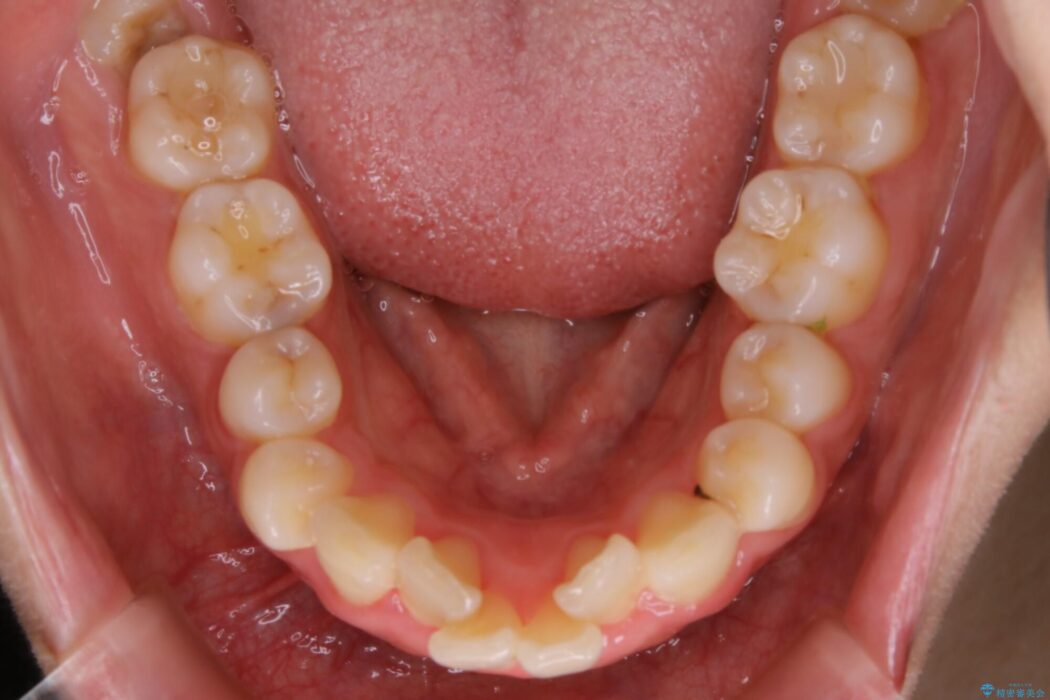

口ゴボに加えて歯列のガタガタを改善したいと来院されました。

患者様のご希望によりインビザライン装置での治療を行いました。

インビザラインは歯を後ろへ動かす動き、非抜歯での矯正治療が得意なため、ワイヤー装置では難しいケースでも対応できる場合があります。

矯正治療において歯並びを整えるためにはスペースが必要になります。

抜歯・歯列幅の拡大・IPR(歯と歯の間を少し削って小さくする)・歯の後方移動などでそのスペースを確保します。

程度にもよりますが口元を下げる治療というと抜歯治療を思い浮かべると思いますが、インビザラインは抜歯をせずとも他の3種類の方法を効率よく活用し治療ができます。